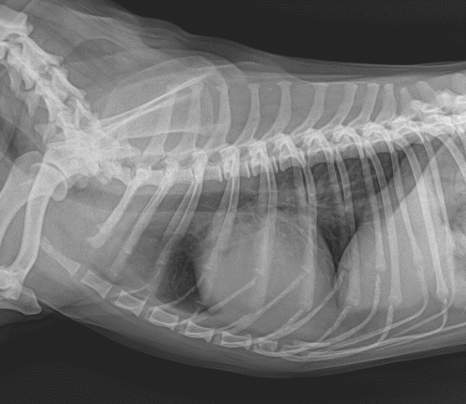

■ 흉부 방사선(X-Ray) 검사 결과

심장 크기의 변화나 폐수종 소견은 확인되지 않았으나, 심장 앞쪽 수준에서 종괴로 의심되는 소견이 발견되었습니다.

강아지 흉선 종양 방사선 (X-Ray)/ 기존 흉부 방사선 (좌) 증상 발생 후 흉부 방사선 (우) /출처: 에스동물메디컬센터 양산점